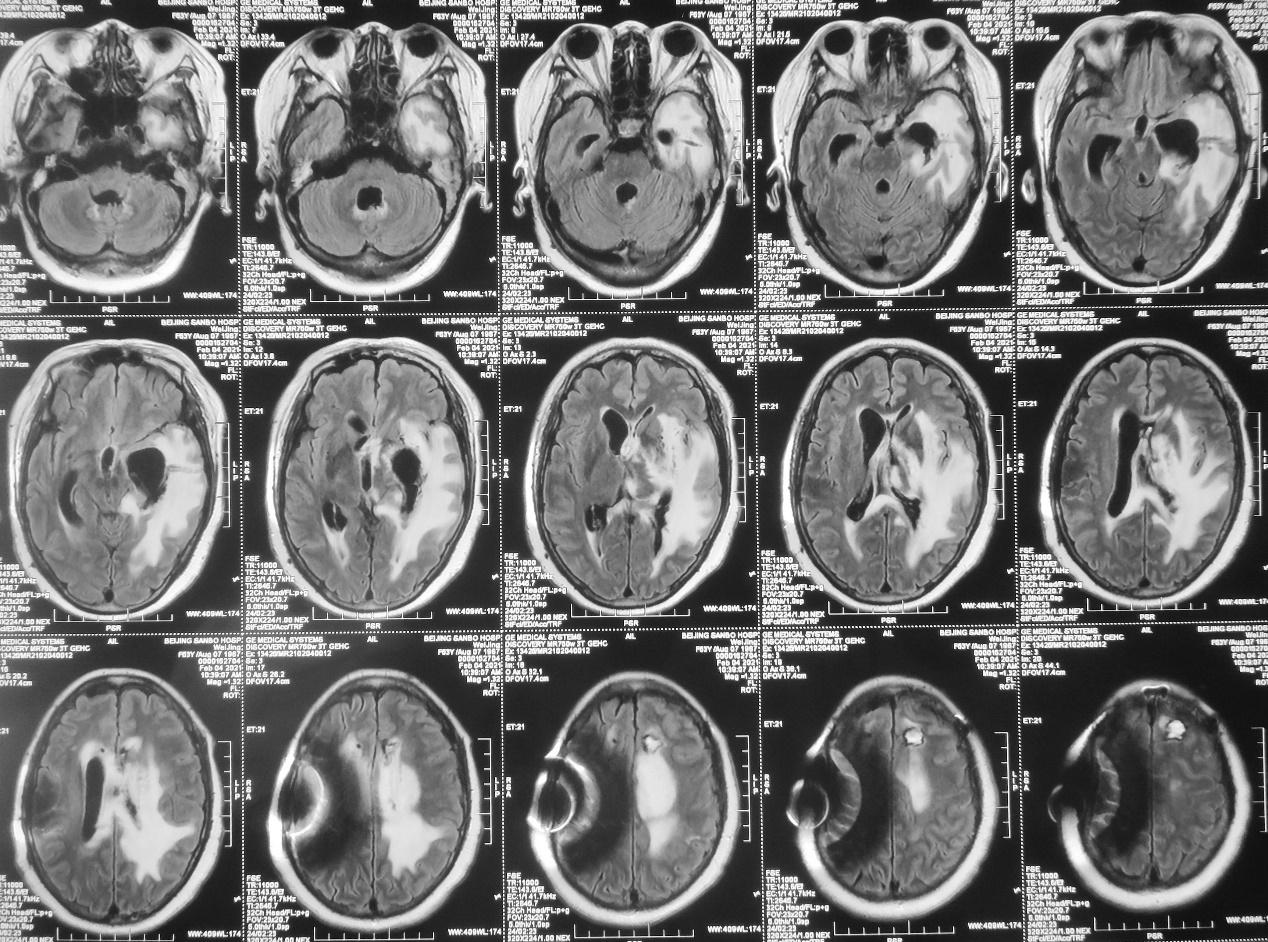

患者病情逐渐加重,出现精神差,饮食差。在当地医生建议下到湖北省武汉市的某三甲医院就诊。于发病后9天即2020年11月17行增强核磁共振检查,发现左丘脑病变明显强化( 图-2 )。当地医生建议手术治疗,但患者担心手术风险较高,于发病后13天即2020年11月21日转到北京某脑科医院。

图-2: 2020年11月17日增强头核磁

发病后24天,抗炎及脑室外引流治疗后11天,即2020年12月2日,精神仍差,间断发热,体温38℃左右,复查头颅增强核磁( 图-7 )见左侧丘脑脓肿病灶环形强化,同时左侧脑室枕角及小脑表面可见强化(感染),提示感染较前范围扩大。

图-7: 2020年12月2日头增强核磁

患者体温正常,仍呈朦胧状态,可自动睁眼,刺激肢体可活动。脓肿清除术后第13天,左侧颞角外引流术后第12天,右侧脑室穿刺术后10天,即2020年12月21日,复查头颅核磁( 图-16 )见脑室缩小,丘脑脓肿病灶缩小,左侧脑室枕角和小脑表面的强化灶消失,提示颅内感染好转。

图-16: 2020年12月21日头增强核磁